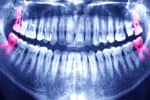

Los expertos dicen que en las últimas décadas, la caries se ha vuelto muy joven. Hoy en día, la formación de manchas en los dientes de los niños ya no es algo sorprendente. Todos los padres se preguntan si es necesario tratar tales problemas o si simplemente se puede quitar un diente malo para siempre.

Dado que el esmalte de los niños es mucho menos duro que el esmalte de los adultos, las enfermedades se desarrollan mucho más rápido. Por ejemplo, incluso una caries pequeña en solo dos o tres semanas puede convertirse en un agujero profundo y doloroso. Tal lesión está cargada con el desarrollo de pulpitis y otras dolencias desagradables.